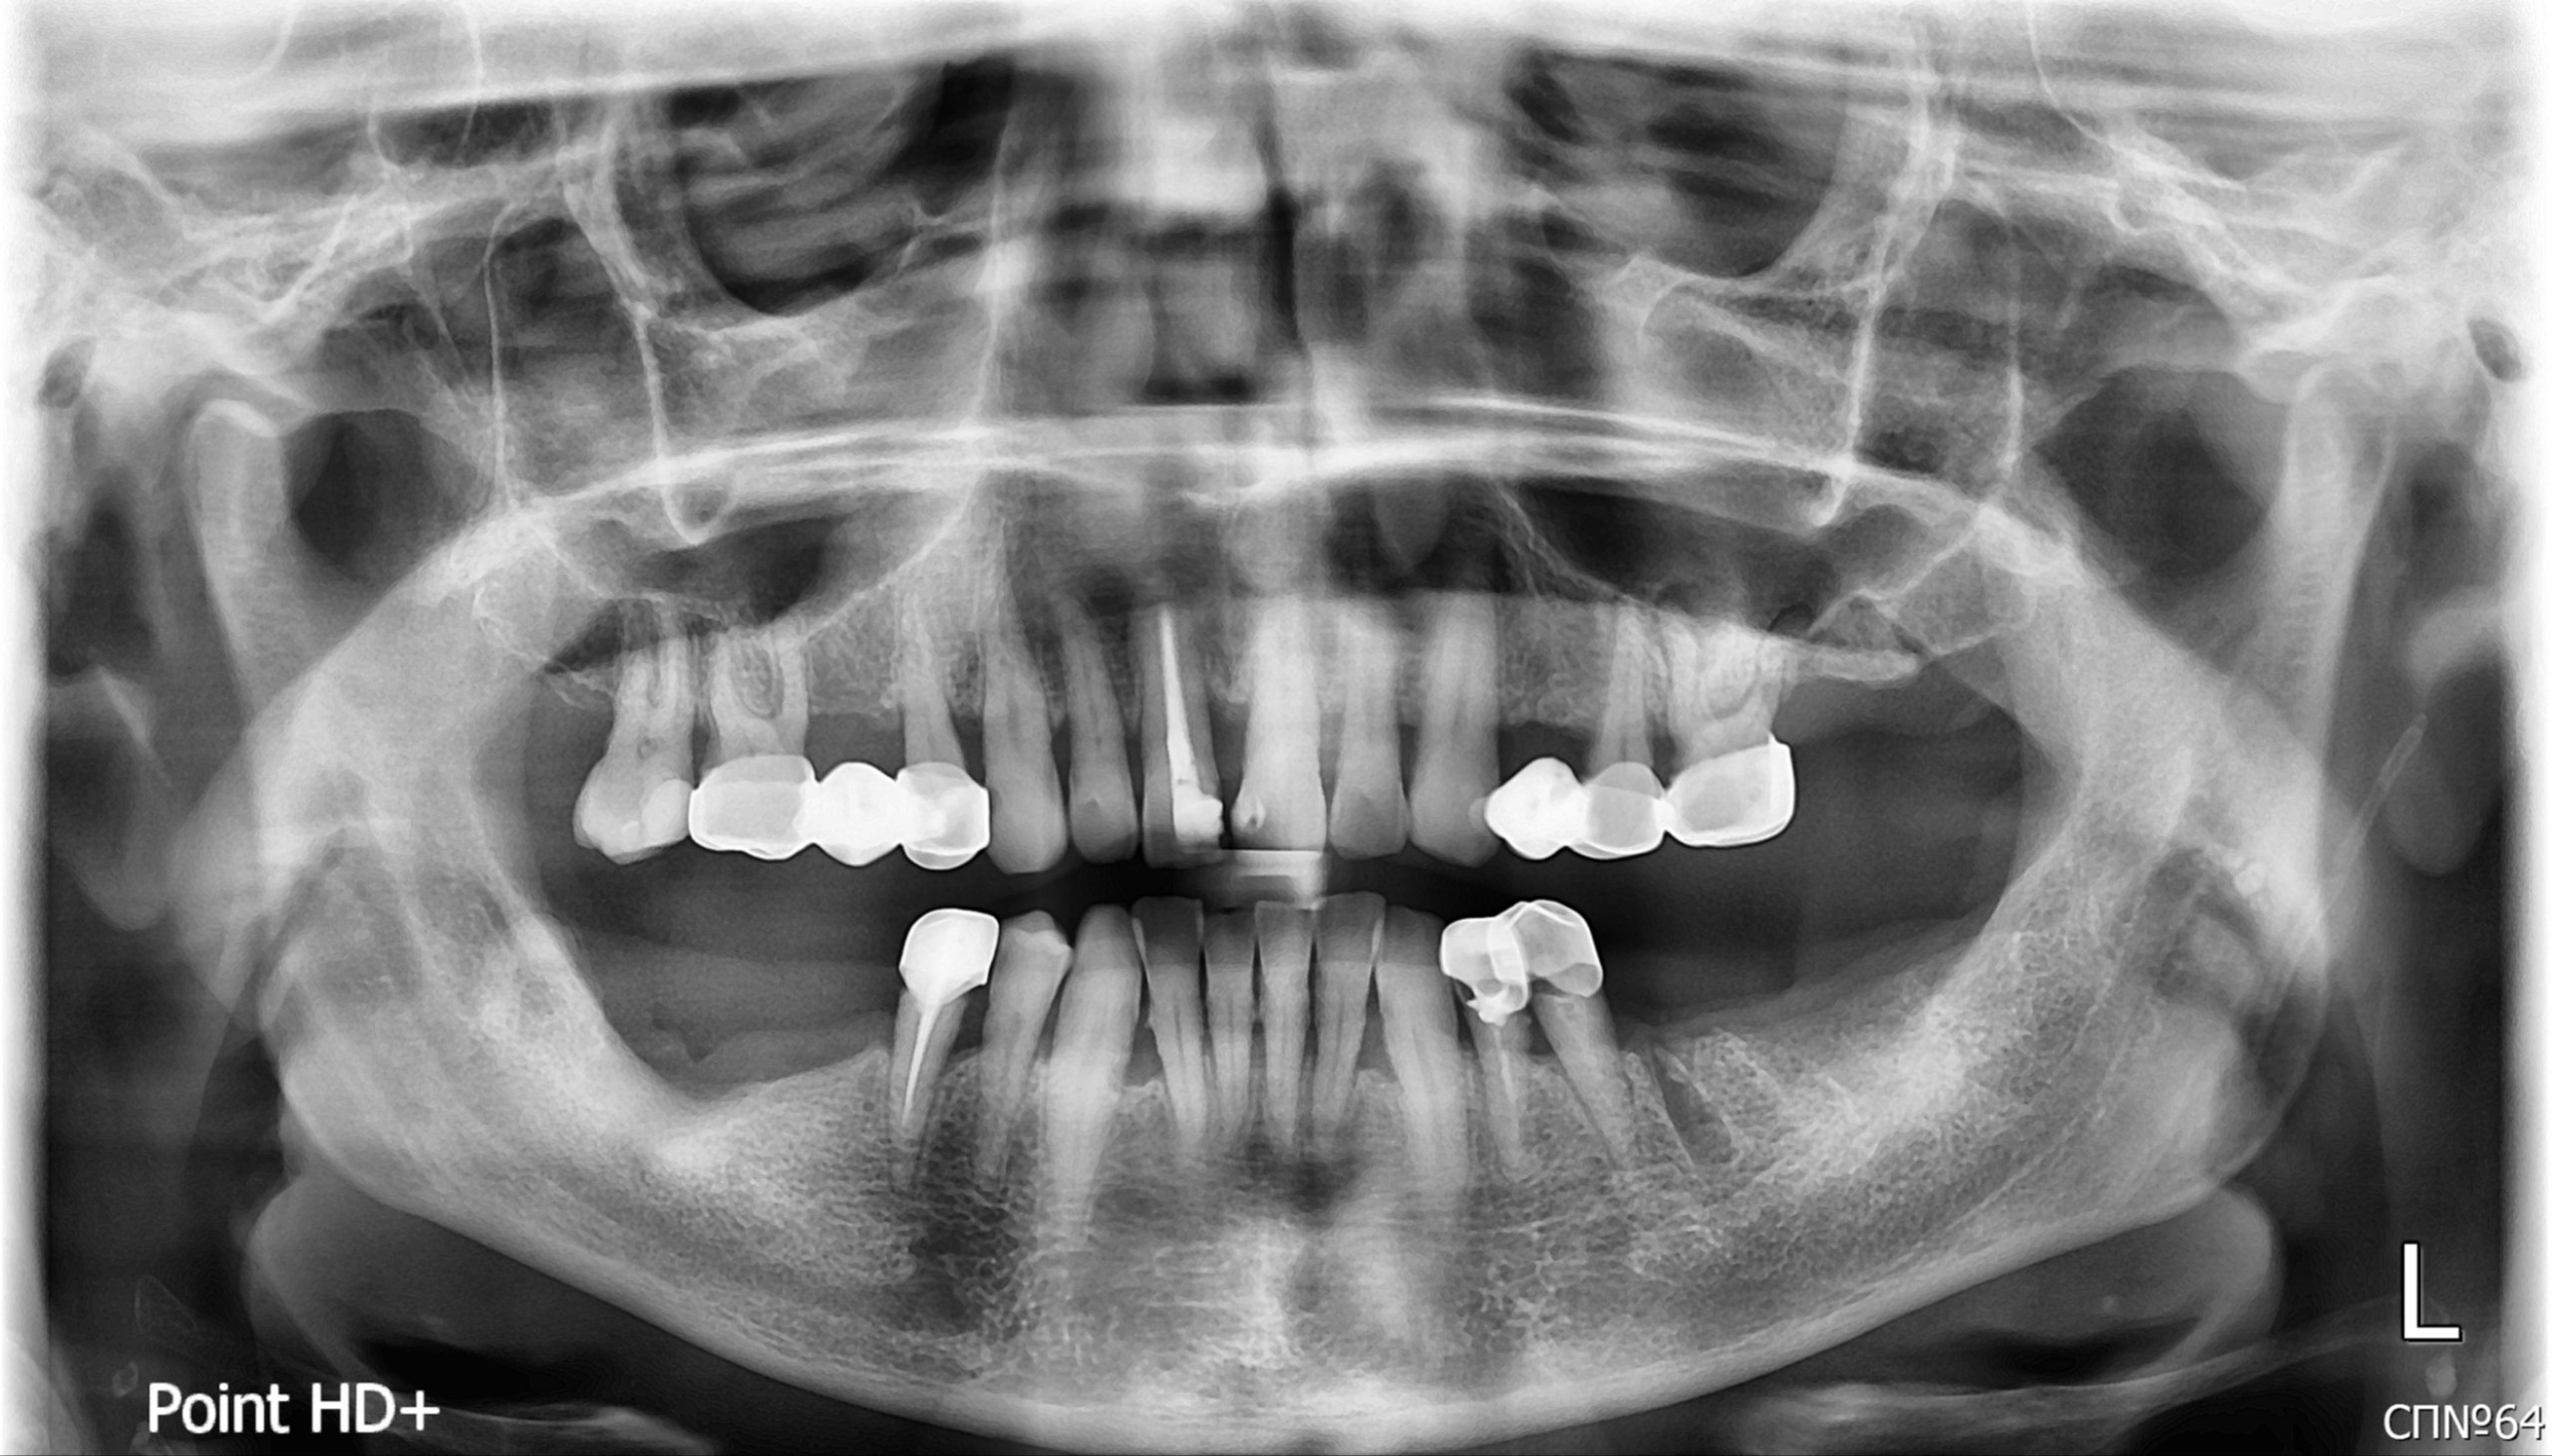

Пациентка обратилась с жалобами на регулярное припухание десны и выделение гнойного содержимого в области левого верхнего моляра (зуб 26). Также отмечала неудовлетворительное состояние старых коронок, нарушение их прилегания, убыль десны. Отсутствие больших жевательных зубов на нижней челюсти. Активных болевых ощущений не было, но присутствовал хронический дискомфорт и эстетическая неудовлетворённость.

Из анамнеза выяснено, что зуб 26 был эндодонтически лечен и покрыт коронкой более 20 лет назад. Пациентка длительное время не посещала стоматолога для профилактических осмотров. Имелись множественные старые реставрации, коронки, часть зубов была девитализирована (удалён нерв) с применением резорцин-формалинового метода, что является устаревшей методикой. Пациентка отмечала, что ранее проводилось протезирование, но со временем коронки потеряли герметичность.

При визуальном осмотре и зондировании выявлено:

- Состояние мягких тканей: Слизистая оболочка полости рта бледно-розовая, умеренно увлажнена. В области зуба 26 — отёчность и гиперемия десны, свищевой ход с отделяемым.

- Состояние зубных рядов:

- верхняя челюсть: Зуб 11 – покрыт пломбой, изменен в цвете (темный окрас), развернут вдоль вертикальной оси наружу.

- зубы 16-15, 24-26 — под старыми конструкциями (металлокерамические мосты и коронки).

- при обследовании выявлены: кариозные поражения (13, 17), несостоятельные пломбы, признаки хронического воспаления у верхушек корней (периодонтит) зуб 26.

- нижняя челюсть: Отсутствуют жевательные зубы 38, 37, 36, 46, 47 48 . Зубы 33, 32, 31, 41, 42, 43, 44 требуют ортопедического лечения. Коронки на зубах 34, 35 — штампованные, с нарушением прилегания и рецессией десны до 3 мм. Зубы 34, 35, 45 — девитальные, с признаками некачественного эндодонтического лечения (резорцин-формалиновый метод). - Функциональные пробы: Перкуссия зуба 26 умеренно болезненна. Пальпация по переходной складке в проекции корней болезненна. Подвижность зуба 26 — I степени.

- Компьютерная томография (КЛКТ) челюстно-лицевой области: на 3D-снимках детально визуализированы:

- состояние костной ткани, её объём и плотность в областях отсутствующих зубов (36, 46) для планирования имплантации;

- признаки хронического воспаления у верхушек корней зуба 26 (периапикальные разрежения костной ткани);

- качество ранее проведённого эндодонтического лечения (в каналах зубов 26, 34, 35, 45 следы пломбировочного материала не определялись или были неудовлетворительными);

- анатомические особенности: у зуба 26 выявлено 4 канала, в дистальном корне — апикальное искривление, в медиальном — возможная трещина в области фуркации (разветвления), устье дополнительного канала (MB2) не обнаружено;

- генерализованная убыль альвеолярной кости на 1\2 длины корней зубов (Хронический пародонтит). - Диагностическое восковое моделирование (Wax-Up): для зубов 13, 12, 11, 21, 22 и планируемых коронок на нижней челюсти выполнены восковые модели будущих реставраций. Это позволило оценить будущую эстетику, функциональность и согласовать план лечения с пациенткой.